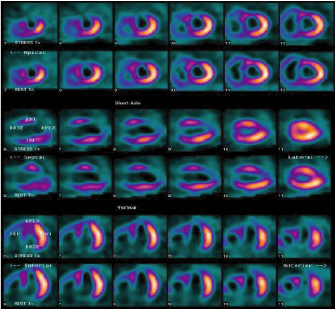

Cardiología nuclear

Los estudios de medicina nuclear en cardiología o cardiología nuclear son auxiliares diagnósticos que utilizan diversos radiotrazadores de baja energía que al ser inyectados por la vena al paciente, emiten rayos gama que son captados por un tomógrafo especial (SPECT cardiaco).

Estos radiotrazadores demuestran cuanta sangre llega al músculo cardiaco a través de las arterias coronarias, a esto se le

conoce como evaluación de la perfusión miocárdica. Cuando existe la sospecha de angina de pecho y/o infarto (cardiopatía isquémica) este estudio puede demostrar la disminución de sangre en el musculo cardiaco y su repercusión en la función del corazón.

La evaluación de la perfusión miocárdica con SPECT cardiaco se realiza mediante dos imágenes de 20 minutos, la primera imagen se obtiene una hora después de la inyección del radiotrazador en reposo y la segunda imagen se obtiene después de la inyección del radiotrazador mientras que el paciente hace una prueba de esfuerzo en banda sin fin o bien, para las personas que no pueden hacer ejercicio físico, con la administración de un medicamento. Todo el proceso tiene una duración de 3 a 4 horas y esta supervisado por especialistas en cardiología nuclear.